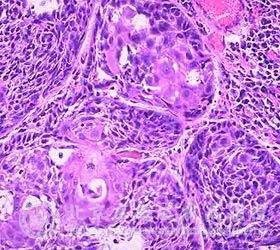

口腔鳞状*癌是发生在口腔的一种癌变,一般发生在下唇的约有38 ,总体上的情况为5年生存率为90 ,一般不会转移.若癌变发生在上唇则更具侵略性,治疗口腔鳞状*癌时,要在唇的大部分呈现恶变前进行,一般需进行外科手术或用激光切去所有被侵及的粘膜。手术过后,建议使用遮光剂并且禁烟。

大约11 的口腔鳞状*癌发生于腭和扁桃体部位.如果在淋巴结未被侵之前治疗,那么患者的5年生存率为68 ,但在淋巴结被侵及后治疗者存活率仅为17 。约有40 的口腔鳞状*癌发生在口底或舌。主要是由于吸烟(特别大量吸烟)和饮酒引起的;吸烟和饮酒对身体造成很大的伤害,容易引发复发及其它的病症。此外,口腔癌病损可出现在红斑或白斑上,在舌上的癌,有淋巴结转移的5年存活率降低至20 ,若无转移则5年的生存率可高一些。对舌癌的治疗主要是外科切除术,或者放射线治疗,或两者联合应用。确诊为淋巴结已受侵害的患者,还需进行颈淋巴清扫术.当有转移发生时,常出现在肺,骨,心脏和心包中,患者因注意预防治疗。